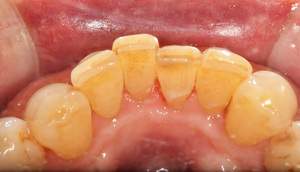

歯石除去

治療前

治療後

| 年齢 | 36歳・男性 |

| 主訴 | 歯石をとりたい |

| 治療内容 | 歯石除去 |

| 治療期間 | 30分 |

| 費用 | 約2,000円 |

| リスク・副作用 | ・歯ぐきの炎症が強いと歯石を取る際に出血することがあります。 ・処置後に歯がしみることがあります。 ・歯と歯の間に隙間ができるので、息が漏れ発音しにくいと感じることがあります。 ・歯ぐきの炎症が軽減すると歯ぐきが引き締まり、歯が長く見えることがあります。 |